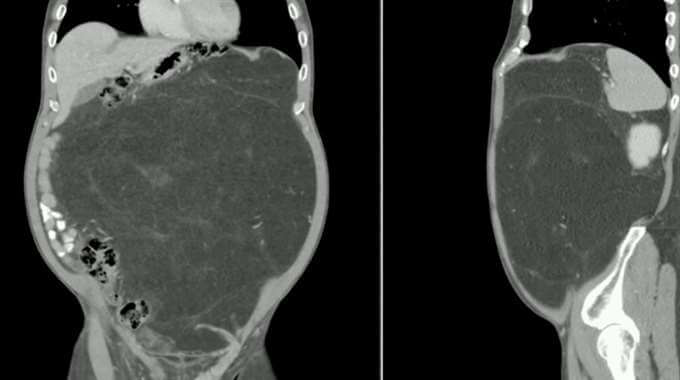

Hans läkare höll med om att hans mage behövde en närmare titt och en skanning visade en enorm tillväxt.

Tumören gav en annan överraskning under operationen – kirurgerna trodde att den skulle vara ca 12 kg. Men istället var den 30 kg. Men efter flera timmar hade dom tagit bort Dalys tumör och en njure.